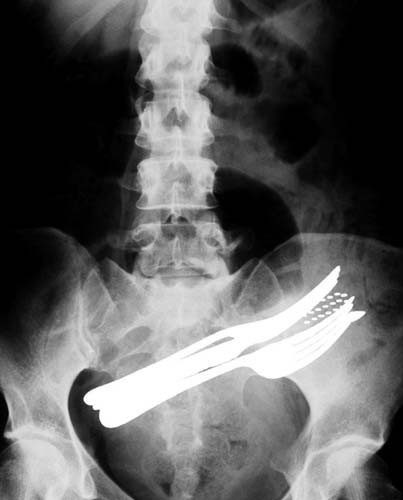

İki çatalı, bir tükenmez kalemi ve diş fırçasını yutmuş bir hasta.

Bu röntgenler gerçek! - Resim: 1